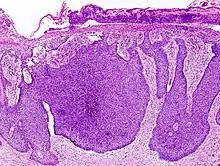

![]() | Lepromatous leprosy | Skin biopsy showing epidermal atrophy and multiple dermal infiltrates. | Category: Histopathology of leprosy | Leprosy |